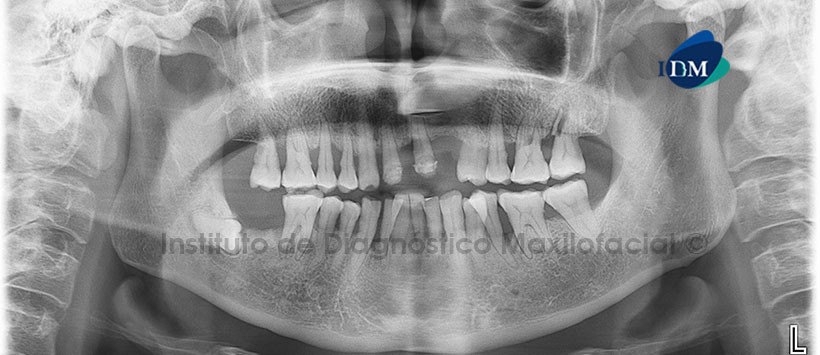

Paciente masculino, 58 años de edad, es referido al Instituto de Diagnóstico Maxilofacial (IDM) para evaluación del sector posterior izquierdo del maxilar superior por presencia de intenso dolor.

En la radiografía panorámica (Figura 1) se aprecia discontinuidad en el contorno radicular de pieza 27 asociada a la presencia de un proceso osteolítico mesial con incremento de la densidad ósea circundante. Se aprecia así también, reabsorción ósea alveolar generalizada con presencia de múltiples defectos óseos. Como hallazgo radiográfico se evidenció a la pieza 23, incluida, en posición mesioangular, con su corona proyectada a nivel periapical de pieza 21 y sobre la sutura intermaxilar.